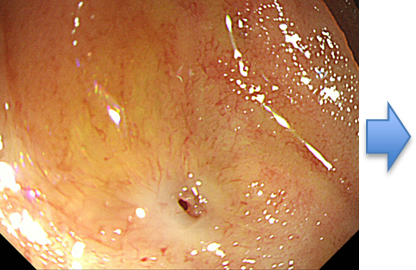

3) 内視鏡的乳頭切除術(パピレクトミー)

• ERCPの画像6